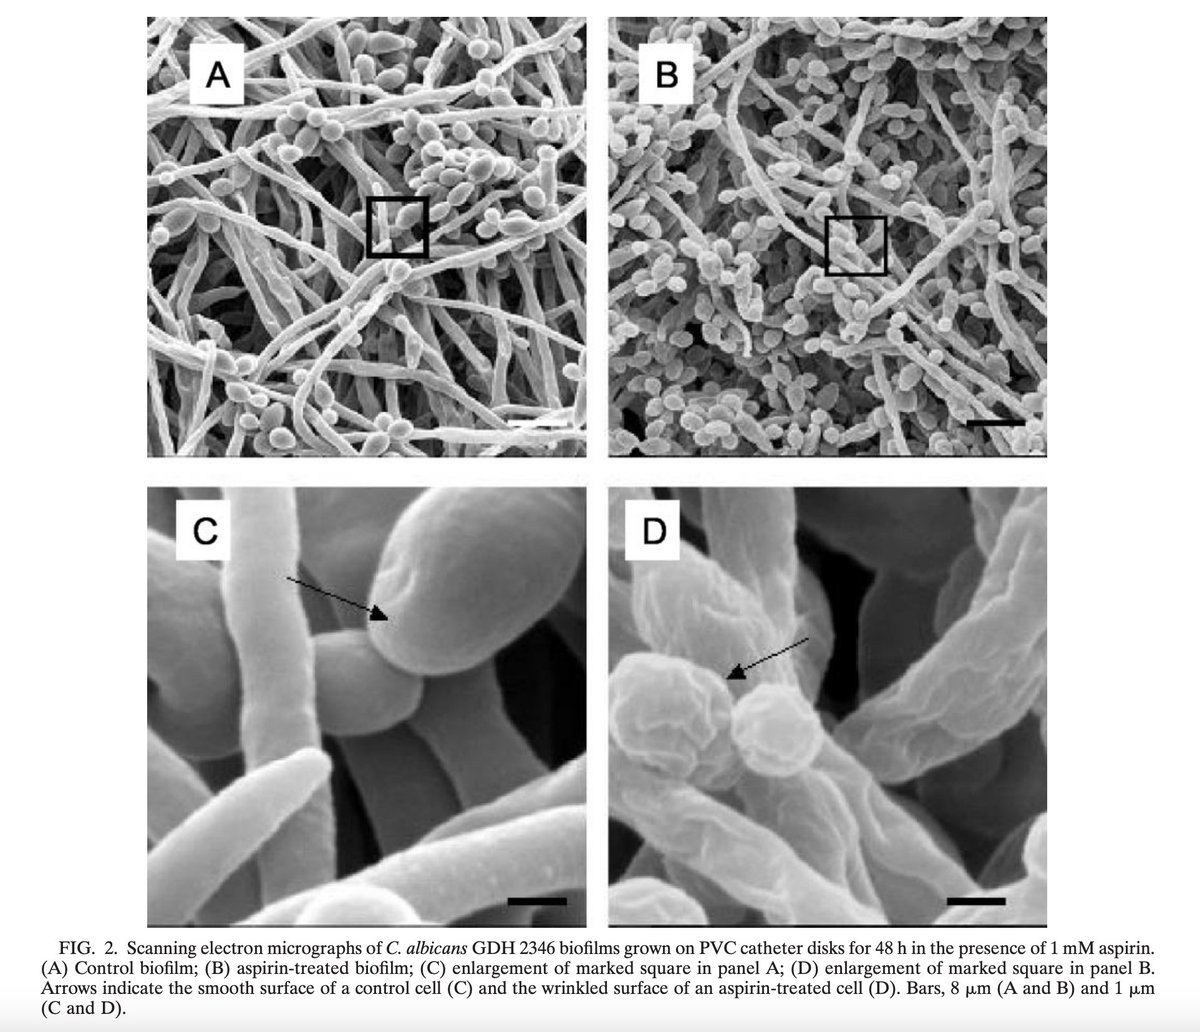

Aspirin also has incredible antibacterial and antifungal effects, even against candida, capable of disrupting biofilm formation that makes it so stubborn and difficult to get rid of.